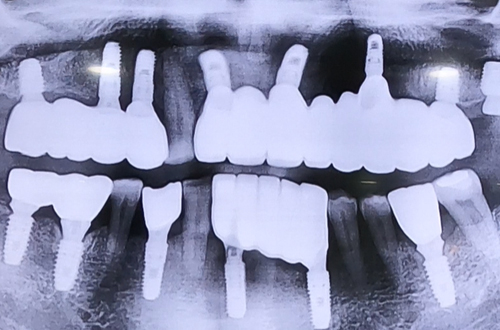

AFTER

임플란트 치료는 시간이 걸리는 치료이고, 그 기간 동안 임시 치아를 해드리지만

저작기능을 제대로 발휘할 수 없으므로, 불편함을 덜어드리기 위하여

씹을 수 있는 치아가 남아 있다면 그 치아를 남기고 전체임플란트를 합니다.

임플란트 식립 후 4개월 간 굳는 기간을 기다리고 예쁘게 보철까지 완성해 드렸습니다.